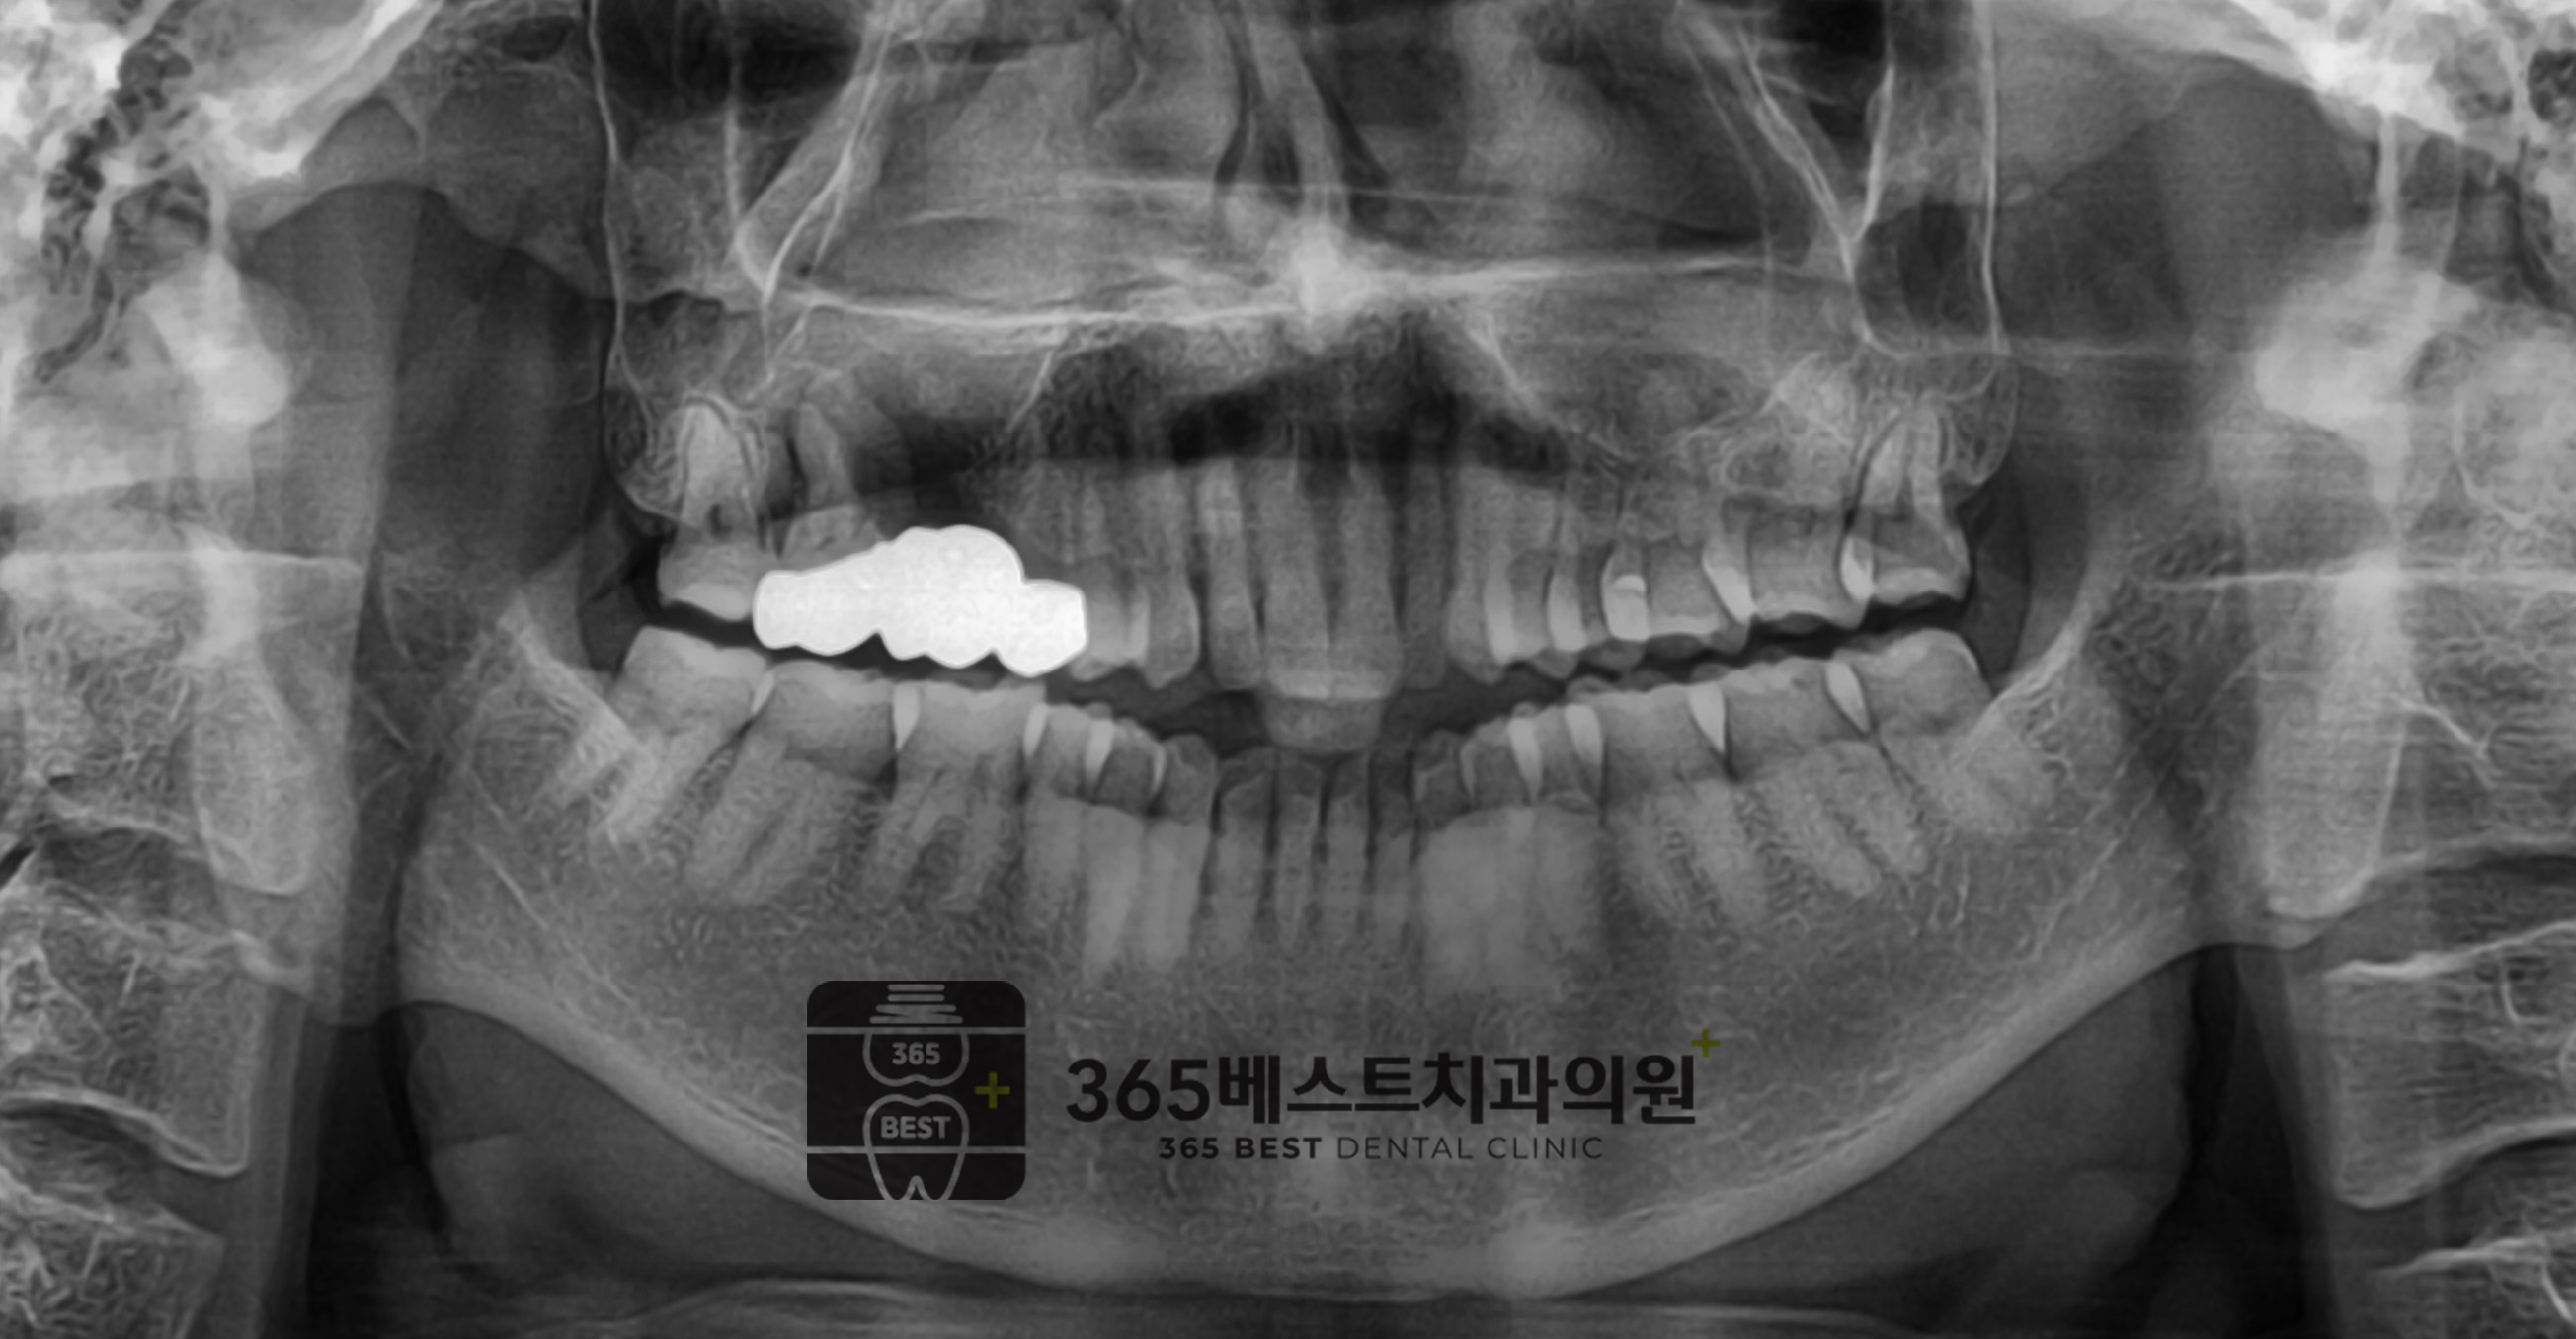

전후사진